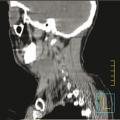

Carcinome épidermoïde du sinus piriforme gauche

CANCER DES VOIES AERODIGESTIVES

CARCINOME EPIDERMOIDE DU SINUS PIRIFORME